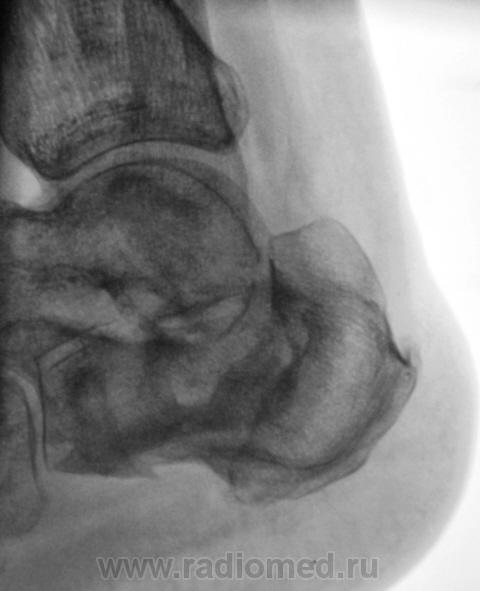

Пациент направлен на рентгенографию пяточных костей с диагнозом "остеомиелит". Год тому, пациент перенес перелом со значительным смещением отломков. Лечили... "как лечили". Сегодня прислали на рентгенографию с подозрением на остеомиелит.

Честно говоря интерпретировать такое не приходилось. Видно дефект кости и видно что он открывается за пределами кости. Так перелом сросся? Раз он как конь на параде, с чего тогда подозрение на остеомиелит?

В пяточной кости, определённо, не хватает костного фрагмента (может осколок удалён при операции); а в бугре пяточной кости - что-то "слишком светло" : как бы нейро-троф. расстройства

не спутать с лилизом (ОМ) - поднимать снимки п/е операции / снятия иммобилизации...

Пусть и дальше топает, как по мне - вариант комрессии с отличной консолидацией, а "псевдополость" - следствие этой самой компресии и оскольчатого перелома в сочетании с деформацией. Деструкции не видно!!!!!

А наружу ничего не открывается? ТИпа свищевого хода? На медиальной поверхности...

Ничего не открывается, да и пациент шагает, как конь "на параде".

Операции не было.

Позвольте, а как же недостающий участок кости - рассосался что-ли или такая "хорошая " компрессия

Видимо рассосался осколок. Только вот что за "дорожка" к наружной поверхности?

Операции не было. Был наложен ГИПС, и все...